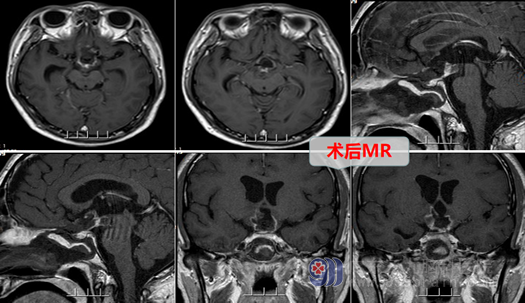

外十科主任欧阳辉教授看了小张拍的检查片子解释道:头部MR显示:鞍上-三脑室底部占位性病变,结合病史,考虑颅咽管瘤可能大,建议补充CT及DWI+ASL+DTI检查。DTI:单体素MRS检查:鞍上-三脑室底部占位性病变感兴趣内表现,仍考虑肿瘤性病变,其余检查结果也都指向诊断为颅咽管瘤。手术指征明确。完善各相关检查后,外十科团队于8月28号在全麻下行内镜扩大经鼻蝶入路颅咽管瘤切除术+颅底重建术+蝶鞍填塞术,手术很顺利,现小张恢复良好,口渴等症状已明显好转,并于近日出院。

影像检查: